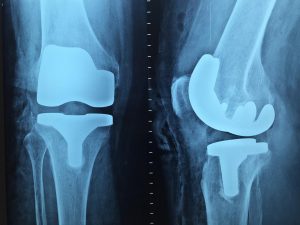

Chirurgische ingrepen zoals gewrichtsvervanging, artroscopie, botbreukreparatie en ligamentreconstructie worden uitgevoerd door ervaren orthopedische chirurgen. Deze procedures zijn vaak nodig om ernstige letsels of degeneratieve aandoeningen aan te pakken die de mobiliteit en levenskwaliteit van de patiënt kunnen beïnvloeden.

Daarnaast heeft de opkomst van 3D-geprinte implantaten de manier veranderd waarop orthopedische chirurgen aandoeningen behandelen. Deze op maat gemaakte implantaten bieden een perfecte pasvorm voor patiënten en bevorderen een sneller herstel. In Nijmegen worden deze technologieën actief gebruikt bij procedures zoals gewrichtsvervanging en reconstructieve chirurgie, waardoor de mobiliteit en levenskwaliteit van patiënten aanzienlijk verbeteren.